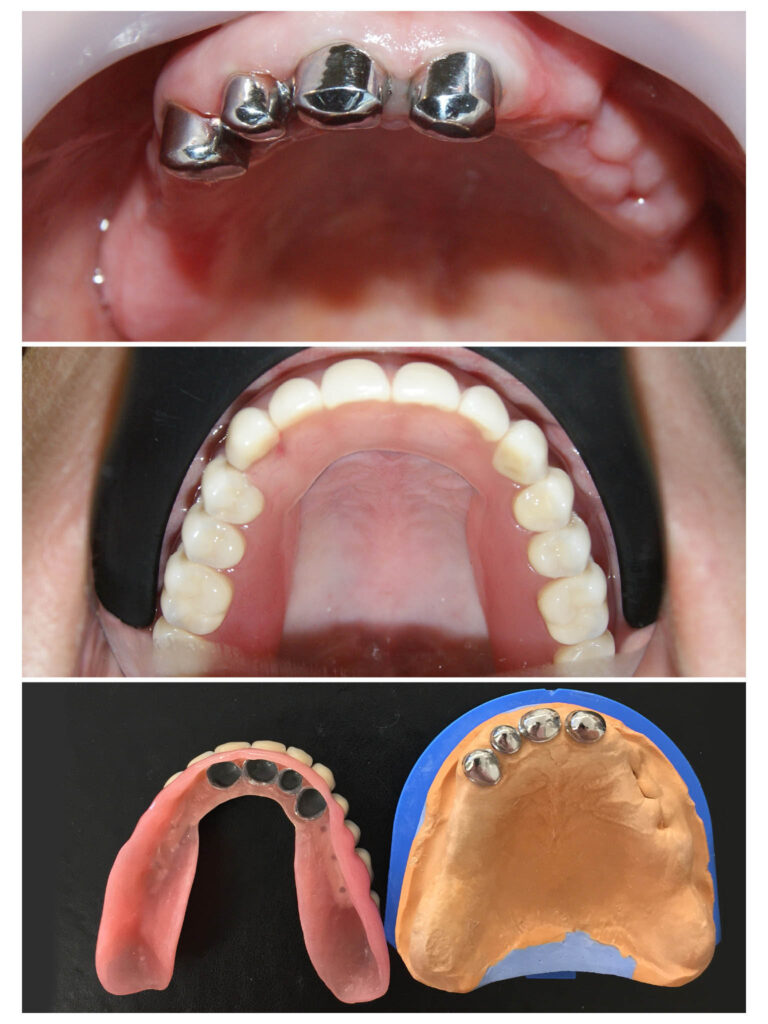

Proteza telescopată  și proteză scheletată aplicate pe dinții tratați corect! Execuția riguroasă oferă stabilitate excelentă.